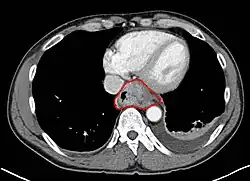

Anatomy

- Length is about 25 cm. Esophageal lesion distance on EGD is typically given from incisors

- Clinically important distance is from incisors to GEJ, which is ~40 cm.

- AJCC divisions of the esophagus: (These are based on adjacent surgical landmarks)

- Cervical esophagus:

- Hypopharynx to the thoracic inlet, which is at the level of the sternal notch.

- By endoscopy, 15 to <20 cm from the incisors

- If thickening of the esophageal wall begins above the sternal notch, the location is cervical

- Upper thoracic esophagus:

- Thoracic inlet to lower border of the azygos vein

- By endoscopy, 20 to <25 cm

- Middle thoracic esophagus:

- Lower border of the azygos vein to the inferior pulmonary veins

- By endoscopy, 25 to <30 cm

- Lower thoracic esophagus and EG junction:

- Inferior pulmonary veins to the stomach; includes the intraabdominal portion of the esophagus

- By endoscopy, 30 to 40 cm